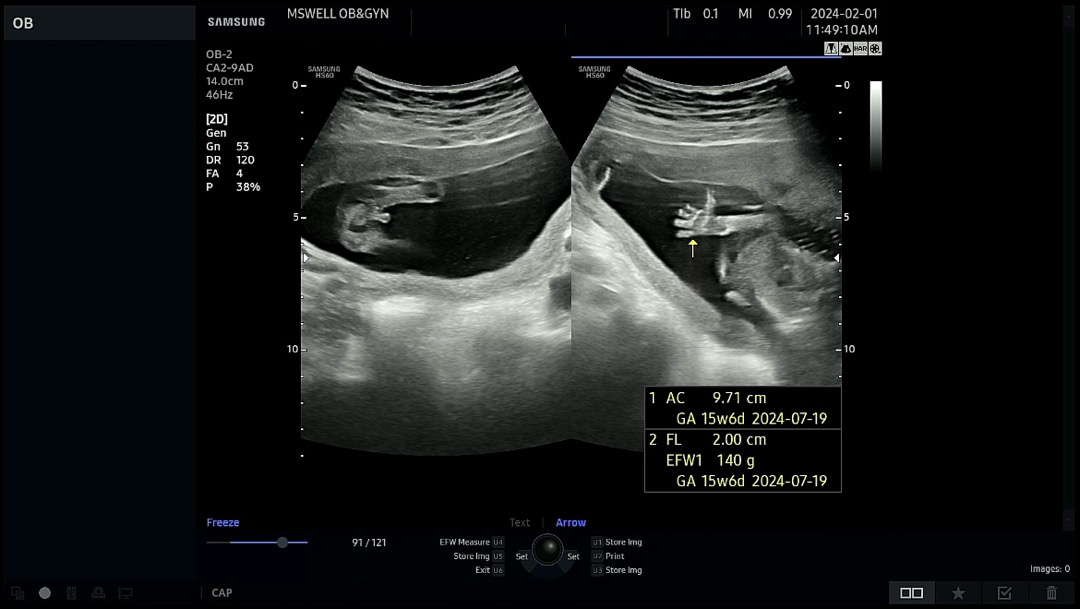

다리사이 미사일🚀

원래 담주에 보러가려했는데 오늘 입덧약 타러 갔다가 성별 확인하고 왔어요ㅋㅋㅋ 시원하게 보여줘서 깜짝 놀랐네용😳 귀여운 손가락 발가락도 구경하고 왔슴다🙌

어머 미사일 확실하네용~ 손가락도 귀여워요